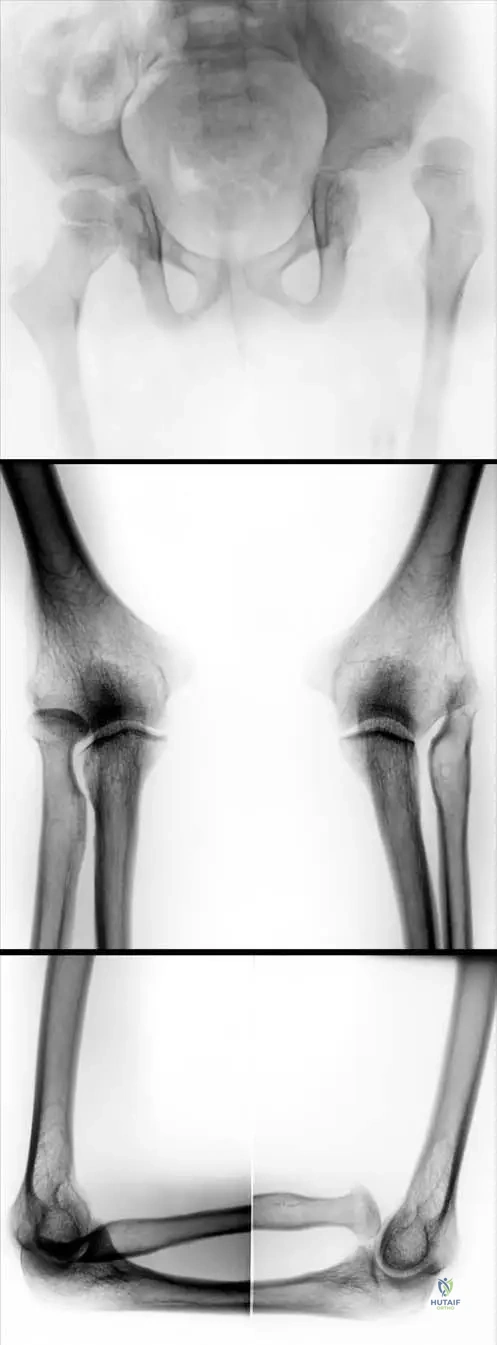

A 15-year-old male presents with a history of easy bruising and skin fragility. On examination, his skin is noted to be remarkably soft and can be stretched significantly beyond normal limits. He also demonstrates excessive range of motion in multiple joints, including his elbows and knees, as shown in the images below. This constellation of findings is most consistent with a disorder primarily affecting which of the following?

Rationale: The clinical features described (easy bruising, skin fragility, skin hyperextensibility, and generalized joint hypermobility) are hallmarks of Ehlers-Danlos Syndrome. The provided text explicitly states that Ehlers-Danlos Syndrome is a "heritable disorder of connective tissue (collagen fibers and mucopolysaccharides)." Therefore, it primarily affects connective tissue. The images further illustrate the excessive mobility of joints, a key feature of connective tissue laxity.

A 32-year-old female presents with chronic joint pain and a history of multiple joint subluxations. On physical examination, she demonstrates the ability to hyperextend her elbows and knees significantly beyond the normal range, as shown in the images. Her skin is also noted to be soft and velvety. These findings are indicative of a generalized disorder characterized by:

Rationale: The vignette describes a patient with chronic joint pain, subluxations, and hyperextensible joints, consistent with Ehlers-Danlos Syndrome. The image further illustrates "Excessive mobility of the joints." The text explicitly lists "generalized joint hypermobility" as a characteristic of Ehlers-Danlos Syndrome. The other options are not consistent with the described clinical picture or the known features of Ehlers-Danlos Syndrome.